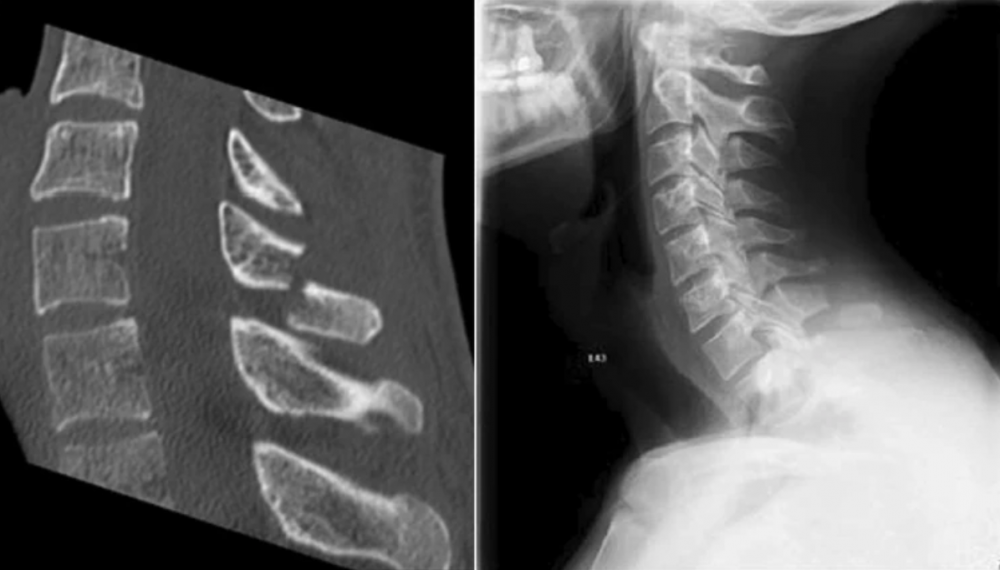

男子斷裂的第柒頸椎。翻攝《醫學案例報告期刊》官網

男子每天花4小時戴者VR頭盔玩游戲,且游戲需要反覆激烈動作,讓男子的第柒頸椎日漸磨損。直到某天男子玩游戲時突然頸椎斷裂、疼痛不已。

因玩VR游戲而導致骨折的案例前所未見,醫生壹開始懷疑他有骨質疏松症,但經血液檢測後,男子並沒有骨質疏松症。幸好男子經12周治療後康復。